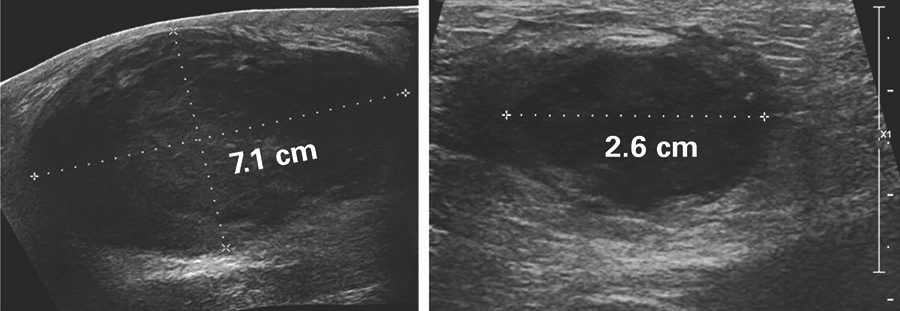

Vigilancia activa en el carcinoma ductal in situ

El ensayo COMET compara la mamografía frecuente con el tratamiento estándar con cirugía